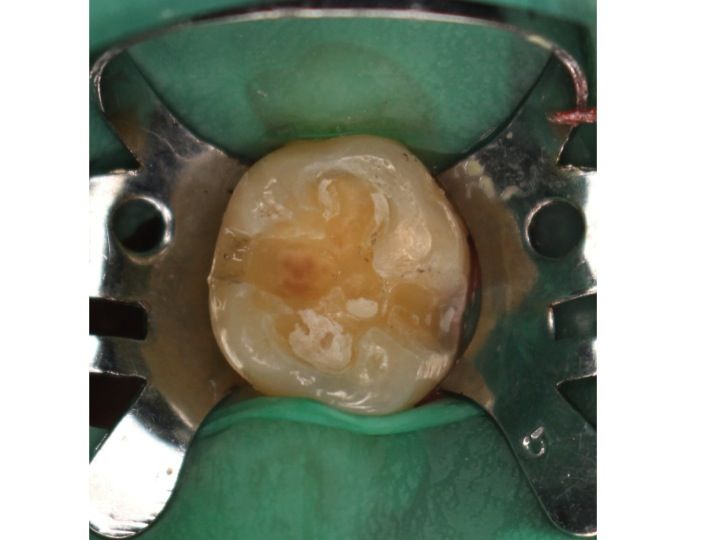

ステップ 2:金属を除去

金属片が口腔内に飛び散らないようにゴムのシート(ラバーダム)を装着し、

金属片および虫歯も除去

削った穴につめたCRをきれいに研磨し、終了です。

次に上顎左側の奥歯です。

*印の歯の治療ステップを見てみましょう。

金属片が口腔内に飛び散らないようにゴムのシート(ラバーダム)を装着します。

削ると金属片が飛び散っているのが分かるかと思います。

ラバーダムがなければ大変なことに…